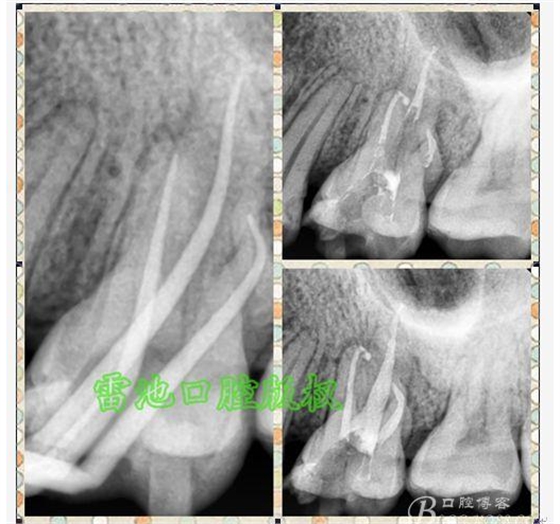

E、X線影像學(xué)的檢查研判能力:這點(diǎn)不需要強(qiáng)調(diào)太多,對(duì)于普通的非CBCT的二維影像對(duì)醫(yī)生讀片能力有一定的要求,有個(gè)逐步提高的過(guò)程,非一蹴而就,需要學(xué)會(huì)把二維的X線影像與三維的解剖結(jié)構(gòu)進(jìn)行良好的對(duì)應(yīng)結(jié)合,對(duì)于某些鈣化的髓室底,應(yīng)通過(guò)想象把根管口的分布、根管的走向以及各種變化通過(guò)想象投射到對(duì)應(yīng)的髓室底上;

1、查閱各種文獻(xiàn),MB2的發(fā)生率在52-96%之間,治療時(shí)遺漏是上頜磨牙根管治療失敗的主因,2、一般位于MB1根管口與腭根管口方向的0.5-5mm范圍內(nèi),而大多數(shù)都位于MB舌側(cè)的1-3mm處,其中2mm以內(nèi)占85.7%,3、MB1-P根管口連線與MB1-MB2根管口的連線夾角大部分(74.3%)在30度以內(nèi);4、MB2的尋找大部分需要去除相應(yīng)部位的牙本質(zhì);5、當(dāng)找到的MB根管口呈“長(zhǎng)線型”且有深色凹線向舌側(cè),或者找到的MB根管口明顯偏頰多提示有MB2的可能;6、DOM(牙科手術(shù)顯微鏡)的使用有助于找尋MB2;